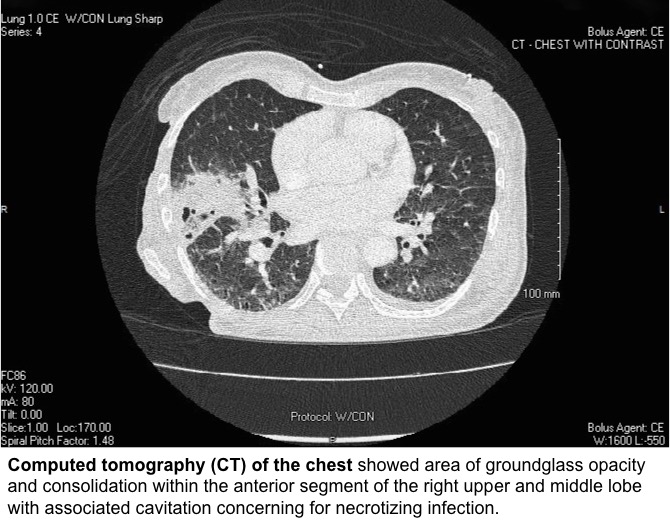

Blood tests were significant for leukocytosis with neutrophil 85.7%, elevated CRP and elevated ESR. She had negative HIV Ab/Ag test. Computed tomography (CT) of the chest revealed consolidation in the right middle lobe with cavitation concerning for necrotizing infection. Blood culture grew Klebsiella pneumoniae that was susceptible to ceftriaxone and was string test negative. Sputum culture grew 2 strains of Klebsiella pneumoniae, one with negative string test and the other with positive string test. Transesophageal echocardiogram found large mobile echogenic vegetation (1.9 x 1.8 cm) on tricuspid valve leaflet. MRI of the spine showed L4-5 discitis osteomyelitis with epidural and paraspinal abscess.